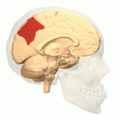

![]() Medial surface of left cerebral hemisphere. (Precuneus visible at top left.) | |

Precuneus of left cerebral hemisphere (shown in red).

Medial surface of left cerebral hemisphere. (Precuneus visible at top left.)- Medial surface of left cerebral hemisphere. (Precuneus colored in red.)